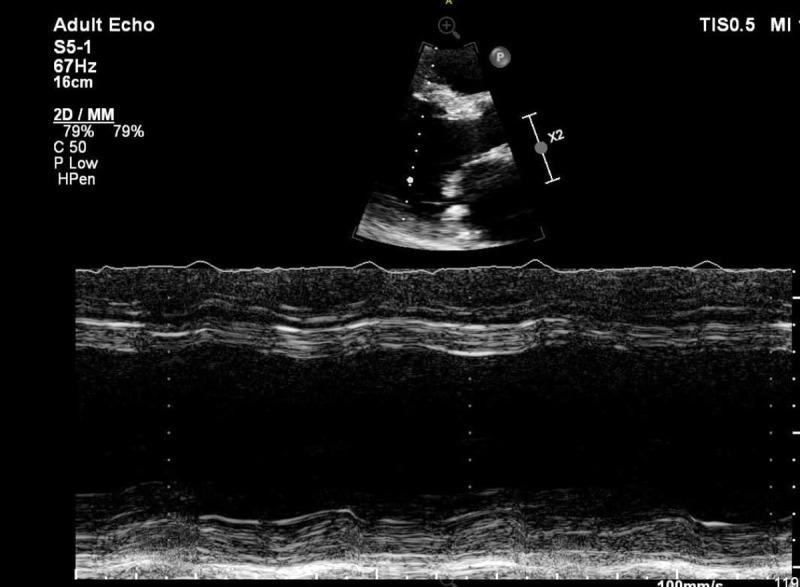

McLeod's syndrome (MLS) is an X-linked disorder caused by mutations in the XK gene with neurological manifestations as well as cardiomyopathy. This is a case of acute exacerbation of heart failure in a 44-year-old White male with a confirmed diagnosis of MLS, which was managed with guideline-directed medical therapy and placement of an implantable cardioverter defibrillator with recovery in ejection fraction.

麦克劳德综合征(MLS)是一种 X 连锁疾病,由 XK 基因突变引起,具有神经表现以及心肌病。这是一位 44 岁白人男性 MLS 确诊病例的心力衰竭急性加重,经指南指导的药物治疗和植入式心脏复律除颤器治疗后射血分数恢复。